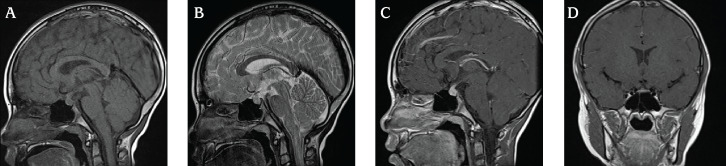

儿童期发作的淋巴细胞性漏斗状尿路垂体炎(LINH)很少报道。通过垂体活检进行病理学评估对于明确诊断LINH是必要的。然而,垂体活检是一种高度侵入性的手术。最近,抗Raphilin-3A抗体(RPH3A-Ab)已被报道为成人LINH的一种有前途的诊断标志物;然而,在儿科人群中很少有这样的报道。我们报告了一例患有中枢性尿崩症(CDI)的8岁男孩,根据RPH3A抗体阳性,他被临床诊断为LINH。他被诊断为CDI,使用脱水测试结合去氨加压素给药。血清和脑脊液肿瘤标志物均为阴性,T1加权磁共振成像(MRI)显示垂体后叶缺乏高信号强度,垂体柄增大。垂体前叶功能检查未发现异常。由于其侵袭性,未进行垂体活检,并开始使用去氨加压素治疗。CDI发病三个月后,患者RPH3A-Ab检测呈阳性。CDI发病9个月后进行的MRI检查显示垂体柄增大有所改善,临床过程证实了我们对LINH的诊断。RPH3A-Ab可能是儿科人群中LINH的早期诊断工具。

Childhood-onset lymphocytic infundibuloneurohypophysitis (LINH) has rarely been reported. Pathological evaluation via pituitary biopsy is necessary for a definitive diagnosis of LINH. However, pituitary biopsy is a highly invasive procedure. Recently, anti-rabphilin-3A antibody (RPH3A-Ab) has been reported as a promising diagnostic marker for LINH in adults but.there are few reports of this association in the pediatric population. We report the case of an 8-year-old boy with central diabetes insipidus (CDI) who was diagnosed clinically with LINH, based on RPH3A-Ab positivity. He was initially diagnosed with CDI using a water deprivation test combined with desmopressin administration. Serum and cerebrospinal fluid tumor markers were negative, and T1-weighted magnetic resonance imaging (MRI) revealed the absence of high signal intensity in the posterior pituitary gland and an enlarged pituitary stalk. Anterior pituitary function tests revealed no abnormalities. No pituitary biopsy was performed because of its invasive nature, and desmopressin treatment was initiated. Three months after the diagnosis of CDI, the patient tested positive for RPH3A-Ab. MRI performed nine months after CDI diagnosis revealed amelioration of the pituitary stalk enlargement, and this clinical course corroborated our diagnosis of LINH. RPH3A-Ab may be useful as an early diagnostic tool for LINH in the pediatric population.